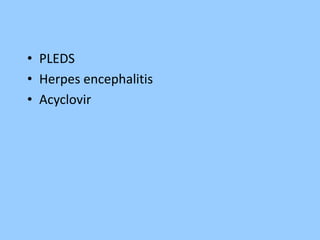

1. The document discusses EEG patterns and findings in various neurological conditions seen in children. It includes descriptions of normal EEG findings as well as abnormal patterns seen in conditions like absence seizures, West syndrome, benign childhood epilepsy with centrotemporal spikes, Lennox-Gastaut syndrome, non-convulsive status epilepticus, subacute sclerosing panencephalitis, and herpes encephalitis.

2. Case studies are presented with clinical histories and EEG findings to illustrate different pathologies. Treatment options are also mentioned for many of the conditions.